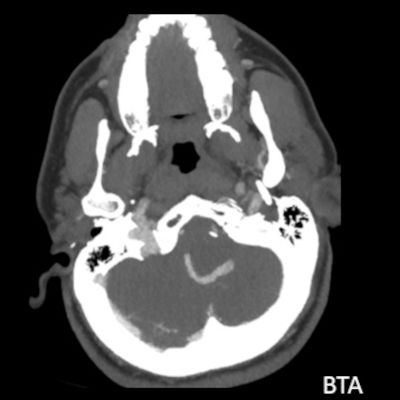

- B. Kontrastsız BT incelemede heterojen dansitede, perferinde kaba kalsifikasyon gösteren kitle lezyonu (ok), BT anjiografi MIP aksiyal kesitte yılan gibi eksantrik bir açık damar görülmektedir (ok). Sağ posterior inferior serebellar arterden (PICA) doluş gösteren tortiyoze dilate vasküler yapı (ok) DSA’ da demonstre edilmiş.

- Heterojen yoğunlukta, yuvarlak veya oval kitle lezyonları olarak görülür.

- Kısmen tromboze oldukları için, lezyon içinde farklı evrelerde kan ürünleri izlenebilir.

- BT anjiyografi (BTA) ile anevrizma içindeki patent, serpantin damar kanalı ve anevrizmanın besleyici damarları daha net bir şekilde görüntülenebilir.

- Kitle etkisi ve çevre dokularda ödem de BT’de görülebilen bulgulardandır.